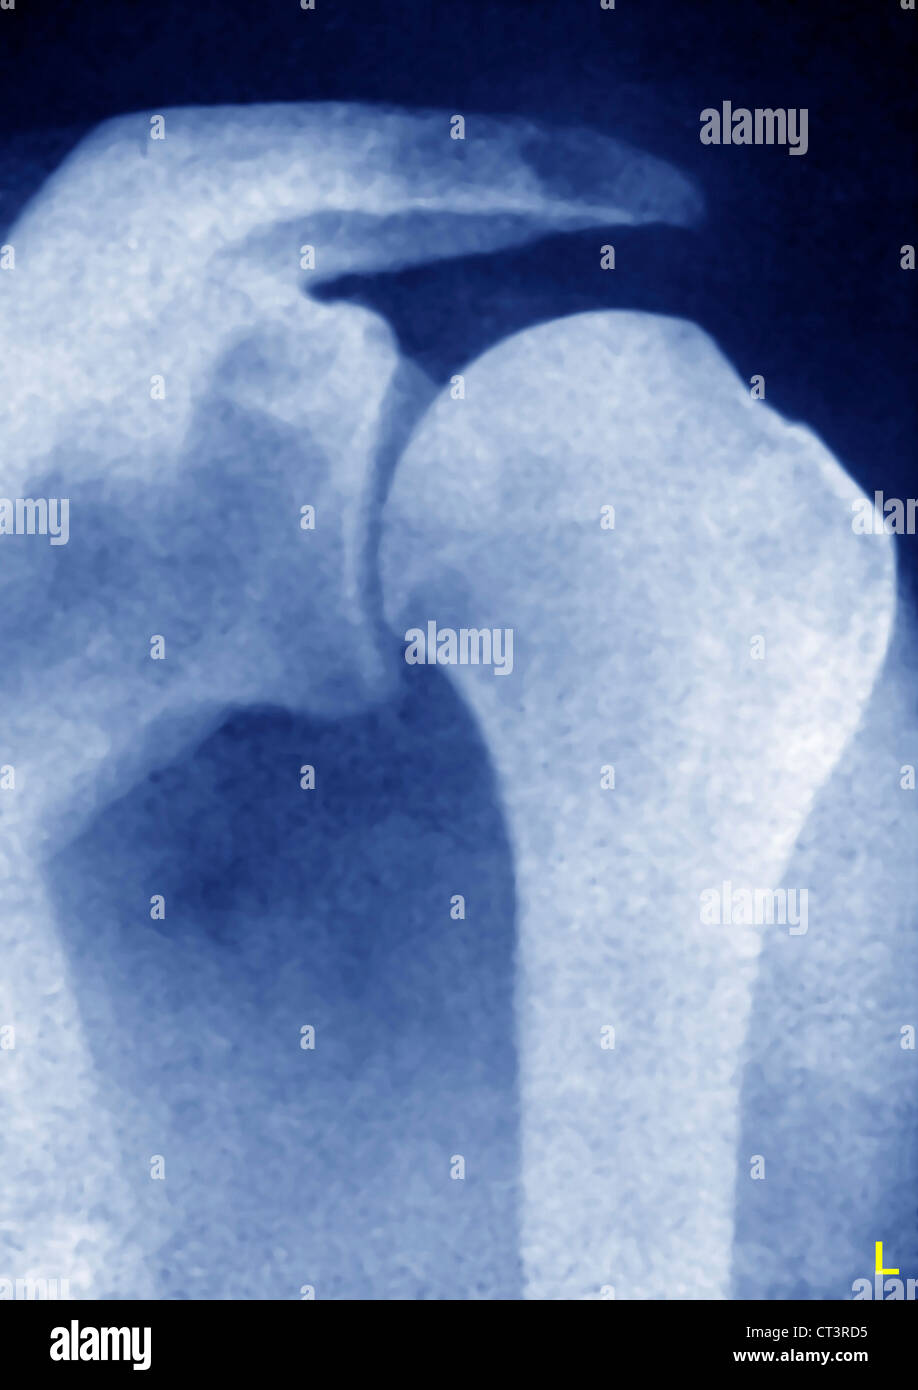

Posterior shoulder dislocation Radiology at St. Vincent's University Hospital

Shoulder Dislocation In Child X Ray . the shoulder dislocation (more accurately termed a glenohumeral joint dislocation) involves separation of the humerus from the glenoid of the. The evaluation of traumatic shoulder injury in children and adolescents will be. Shoulder instability can result from traumatic and atraumatic causes and can be classified as anterior, posterior, or inferior. the most common position for shoulder dislocation/subluxation is abduction and external rotation, and about 70 percent of. they may also order one or more of the following tests to confirm whether you child’s shoulder is dislocated: A test that produces images of.